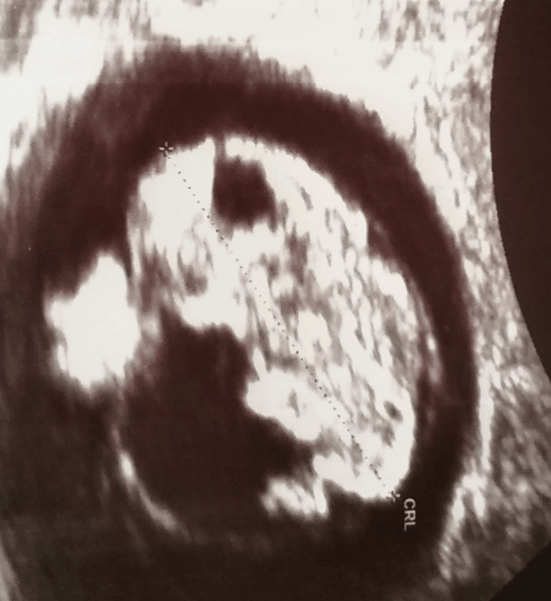

Następna ślicznotka. Cudownie.Zobacz załącznik 837774

Bejbik rośnie zdrowo1,96 cm

Serduszko pika jak ta lala, tylko Pani dr nie pozwoliła jeszcze posłuchać

Następna wizyta za 3 tygodnie.